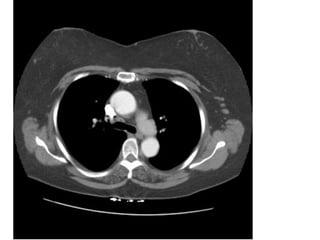

• Chụp CT ngực không cản quang

• Chụp CT ngực có cản quang

Các cửa sổ

• Cửa sổ trung thất

• Cửa sổ phổi

• Cửa sổ màng phổi

• Cửa sổ xương